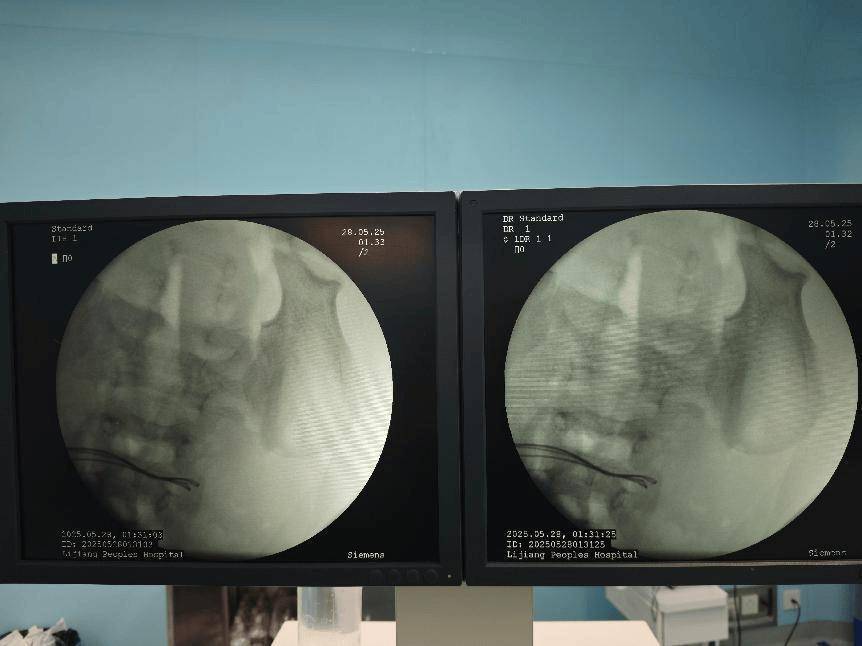

术前腹部DR片

术中完善床旁DR见腹腔内已无异物